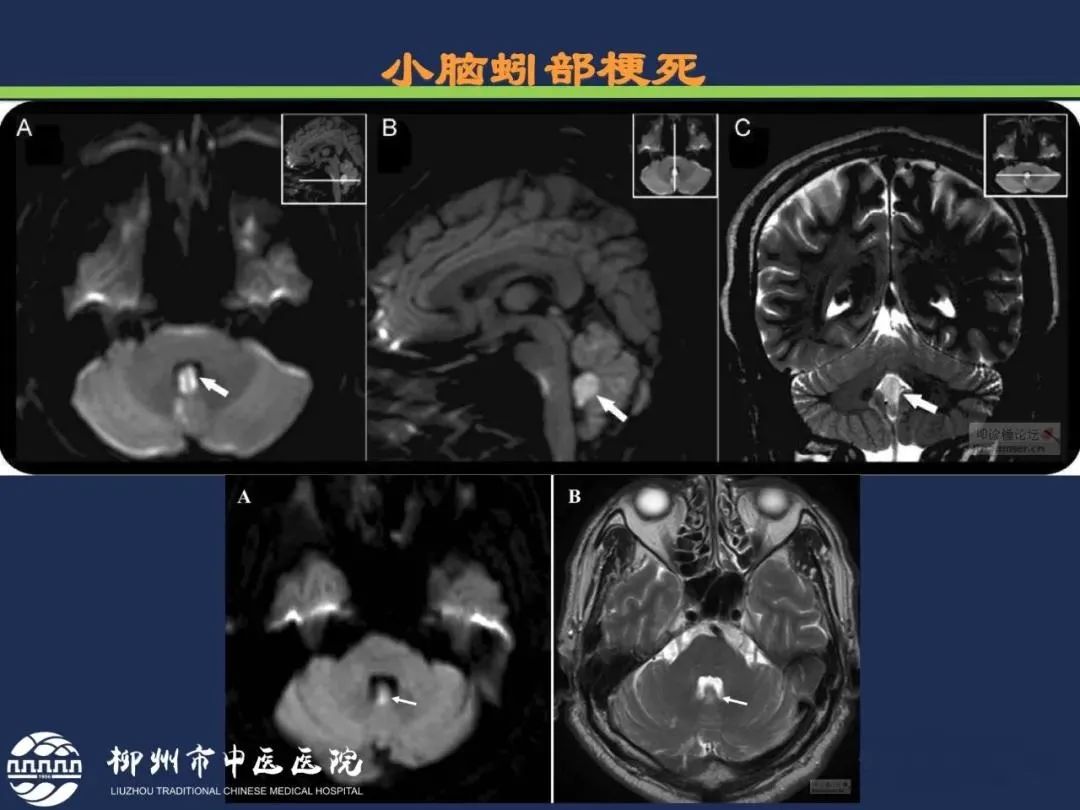

小脑前上动脉